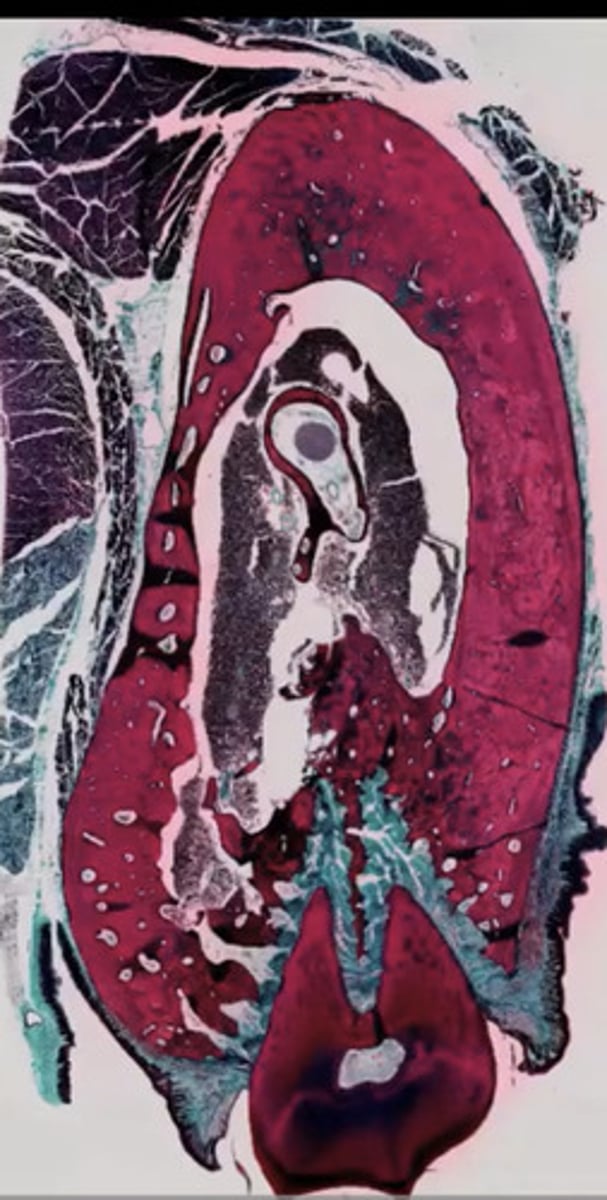

Jajnik (H+E)

Jajnik ciążowy (H+E)